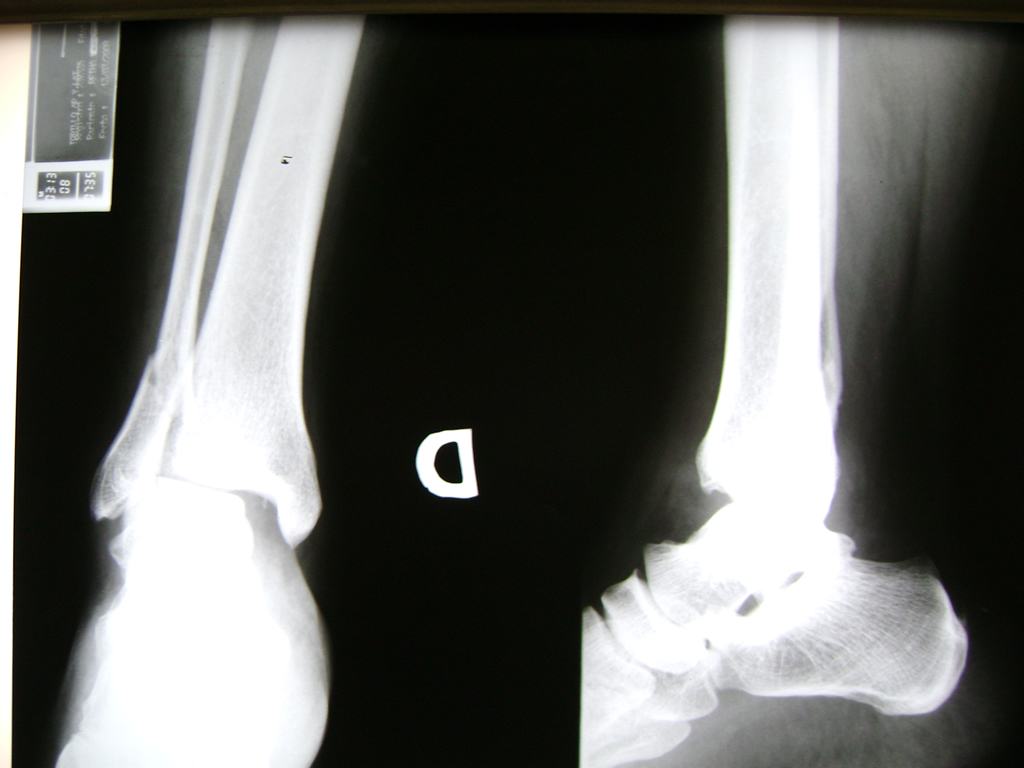

Una fractura de tobillo es la rotura de uno o más de los huesos del tobillo. Estas fracturas pueden ser:

- Parciales (el hueso está sólo parcialmente fisurado, no del todo).

- Completas (el hueso está perforado y está en 2 partes).

- Producirse en uno o ambos lados del tobillo.

Algunas fracturas de tobillo pueden requerir cirugía si:

- Los extremos de los huesos están desalineados entre sí (desplazados).

- La fractura se extiende hasta la articulación del tobillo (fractura intra-articular).

- Los tendones o ligamentos (tejidos que sujetan los músculos y los huesos entre sí) están rotos.